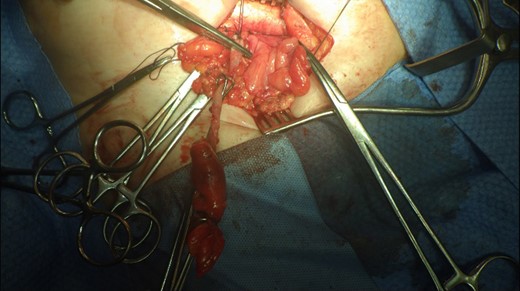

This 82-year-old lady presented with a sudden painful right sided groin swelling not previously noticed. She had no features of obstruction and was opening her bowels and not vomiting. Her medical background included left sided femoral hernia repair in 2005, coronary artery bypass graft and bilateral total knee replacements. On examination her abdomen was soft with the presence of a tender, irreducible swelling in the right groin, inferolateral to the pubic tubercle. She had good bowel sounds and there was stool present in the rectum on PR examination. A full set of blood tests demonstrated no abnormality. A CT abdomen and pelvis demonstrated an incarcerated right sided femoral hernia containing an 8 mm long inflamed appendix with a small amount of localized free fluid and inflammation indicative of De Garengeot’s hernia with underlying acute appendicitis (Fig. 1). The hernia sac diameter measured 2 mm on CT scan. She was taken to theatre for an open Lockwood repair of her femoral hernia and an appendicectomy. Following an initial Lockwood incision over the lump, dissection was performed down to the hernia sac also exposing the inguinal ligament (Fig. 2). The tightness of the femoral ring made mobilization of the appendix difficult. By partially incising the inguinal ligament superior to the femoral ring, the appendix was freed, and on inspection showed inflammation particularly towards the tip (Fig. 3). The caecum was then reduced and the inguinal ligament was repaired with non-absorbable suture. The femoral hernia was then repaired with a small funnel of ultrapro mesh. Appendicectomy was then performed in the usual fashion via the Lockwood incision leaving a slightly longer stump than usual (Fig. 4).

De Garengeot’s hernia – femoral hernia sac containing the vermiform appendix.